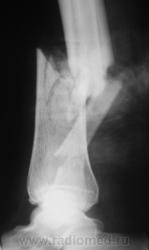

Травма. Вот, такой переломчик...

Травма.  Произведена рентгенография в стандартных проекциях.

Наверное, открытый?

Нет. Закрытый.

Здравствуйте, уважаемый Валентин Львович! Очень похож на "бамперный перелом". У меня вопрос - а почему снимки без шины? Ведь пациенту наверняка было больно при проведении исследования в двух проекциях.

Чегото на боковом структура кости не странная? Как будто в области перелома есть еще дополнительное тенеобразование..     Мягкие ткани?